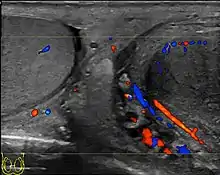

- Ultrasound scanning